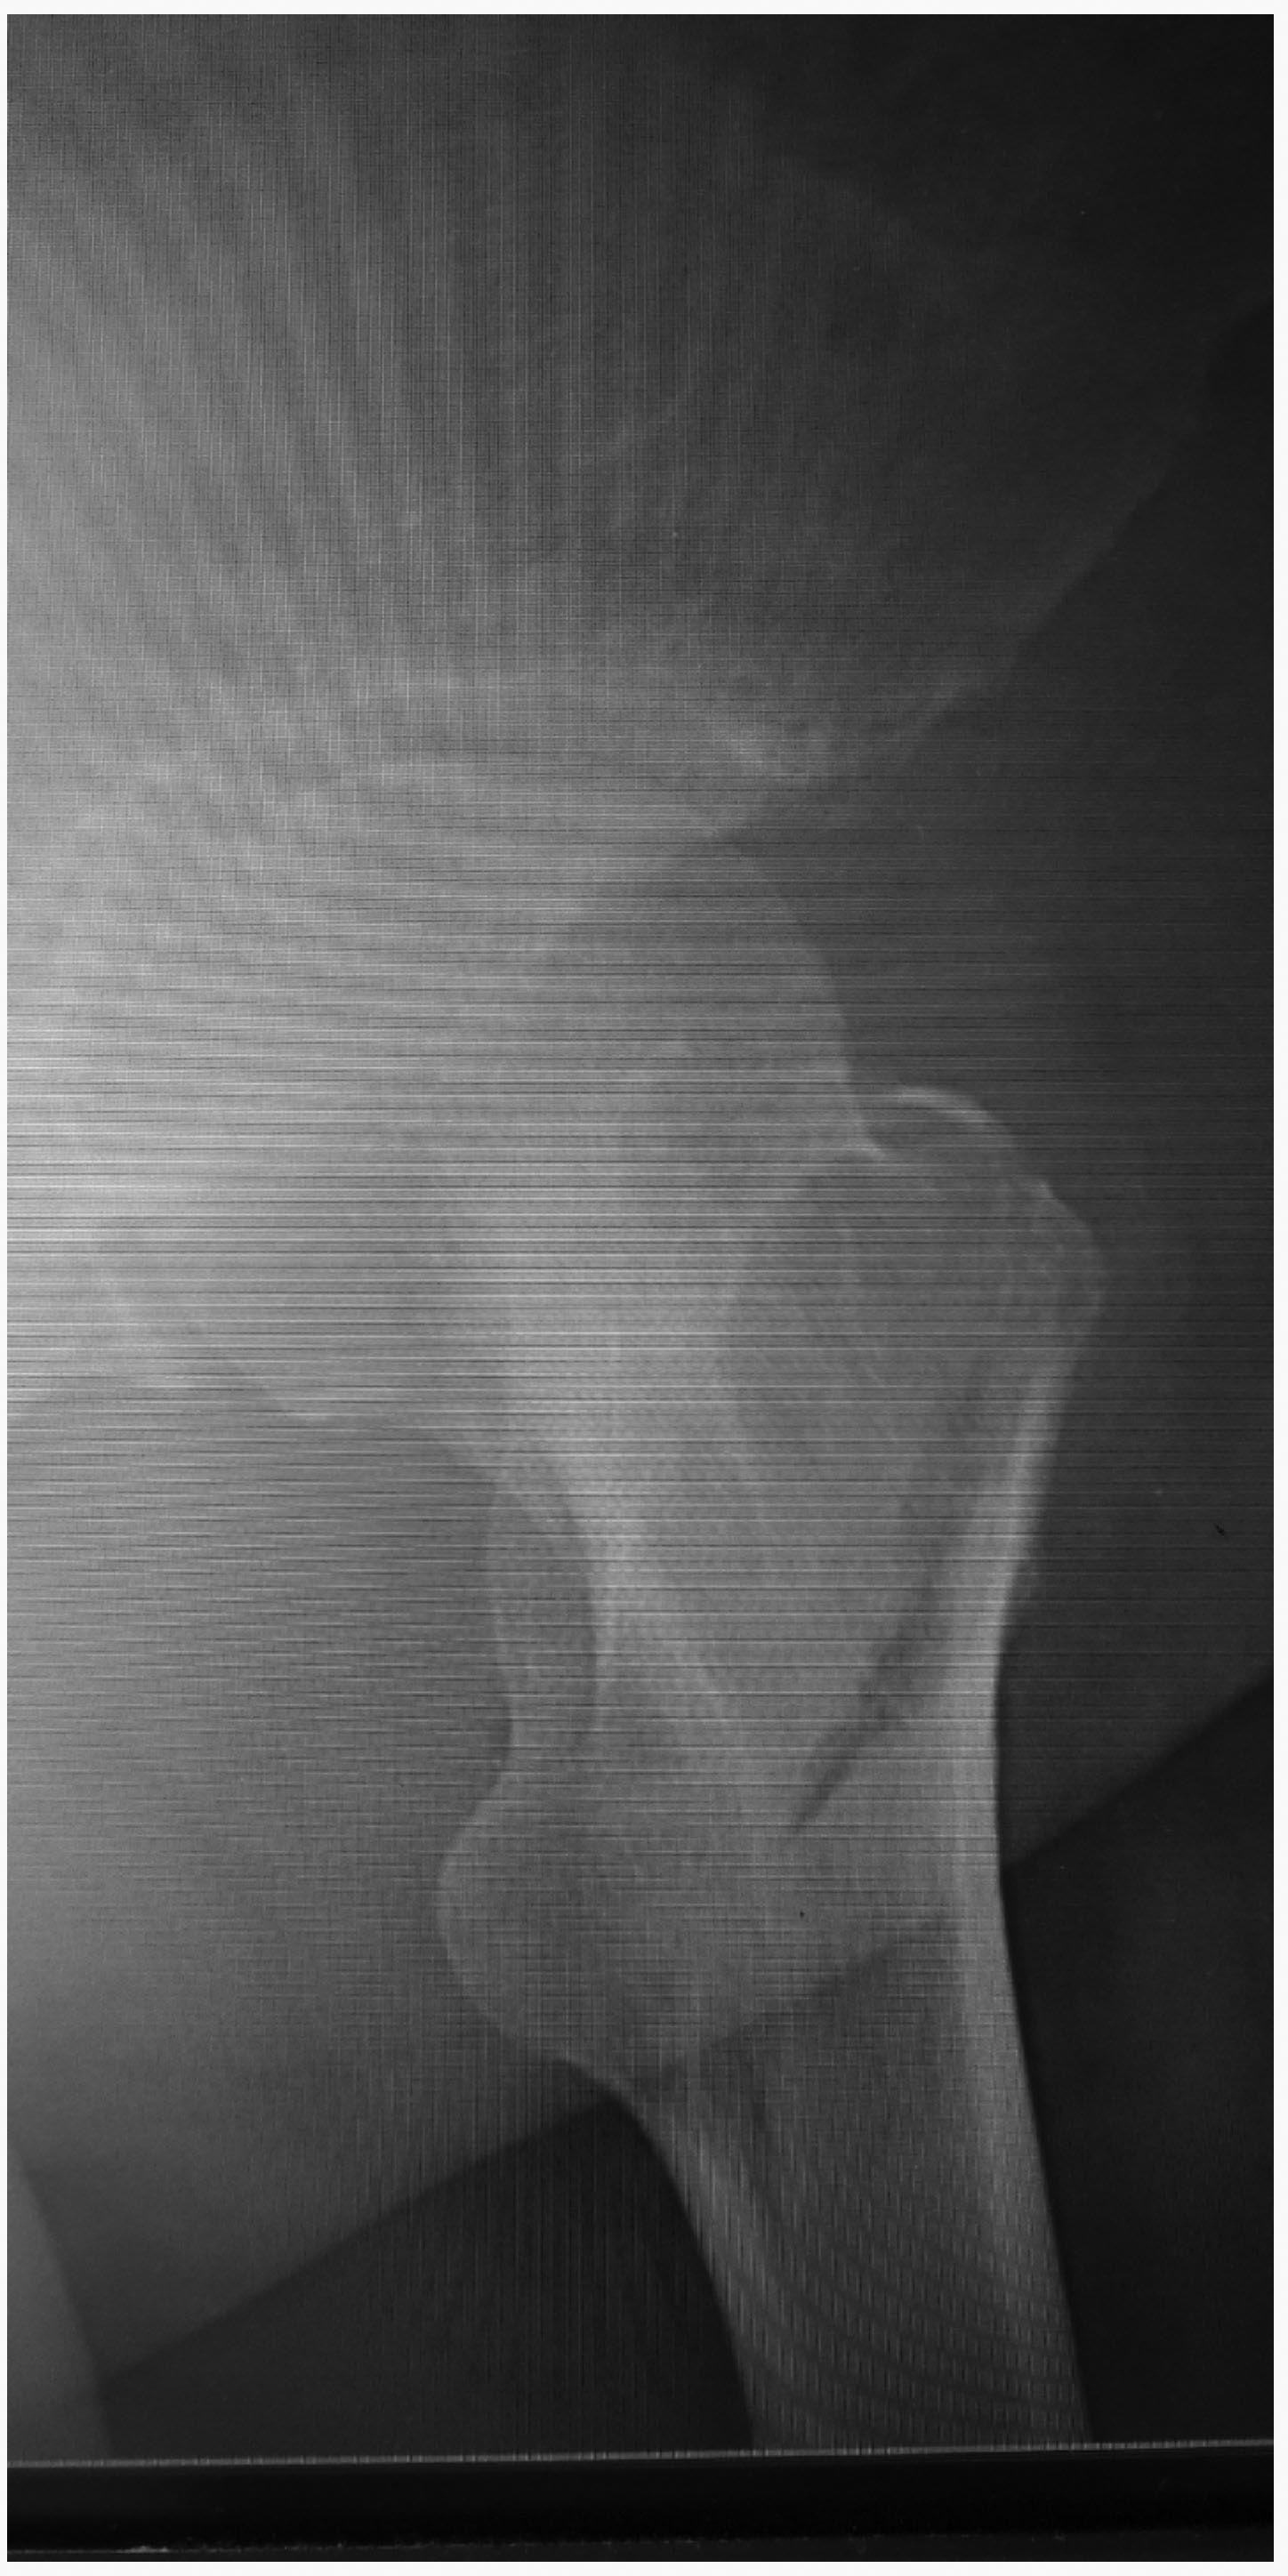

Больная, 77 лет. Соматически и психически сохранная.Есть смысл синтезировать шейку цефаломедуллярным фиксатором или сразу-эндопротез? Если сразу э/протез-смущают субкортикальнын кисты суставных поверхностей.

Зачем КТ, лучше обычную рентгенограмму посмотреть бы. Конечно, надо синтезировать PFN.

Спасибо. Исходно,больная не вызывала впечатление с нарушениями психики, т.к. наблюдали ее днем.В ночные часы больная ходила по палате(на сломанной ноге), не спала, не давала соседкам. Сначала не понятно было, что это, эпизод как реакция на стресс или стойкие нарушения. Днем больная вела себя спокойно. Только при более детальном общении с ней, в т.ч. и психиатра, стало ясно, что присутствуют стойкие нарушения психики, в т.ч. высокая вероятность не соблюдения операции в п/о периоде. Вопрос об операции сформировался на 2 день от поступления и был отправлен на сайт и был о выборе операции. Сначала я ссразу подумал о Y-гвозде по Р-граммам, но решил сделать КТ, где подтвердился субкапитальный, вколоченный перелом шейки.

А так, я больше склонялся к синтезу Y гвоздем, не смотря на перелом и шейки и вертельной области. Интересовало мнение коллег.Rn - граммы конечно есть, качество скромное очень. Даже по ним видно что перелом и шейки и верт.области, по КТ нагляднее.Спасибо.